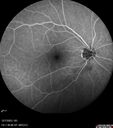

West Nile Virus Multifocal Choroiditis with later CNVM66 views77 year old female with vision loss in the left eye treated with Anti-VEGF